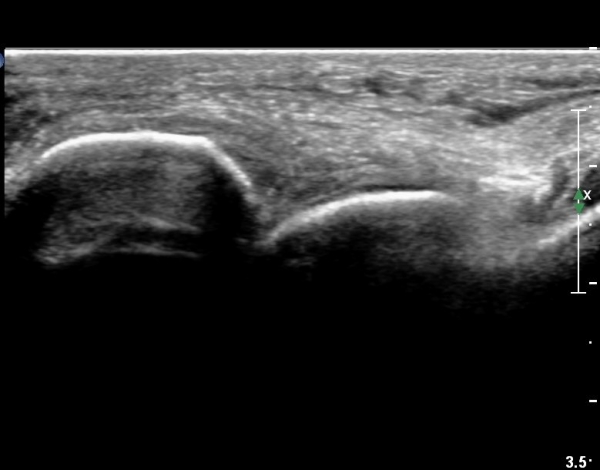

¸»´Ü °æ°ñºñ°ñÀδëÀÇ ÆÄ¿­ÀÌ °üÂûµÇ°í(»çÁø 4, 5)

ºÎÇÏ°Ë»ç ½Ã °æ°ñ°ú ºñ°ñÀÌ ¹ú¾îÁö°í ¼ö¾×ÀÇ À̵¿ÀÌ °üÂûµÈ´Ù(÷ºÎµ¿¿µ»ó 1)